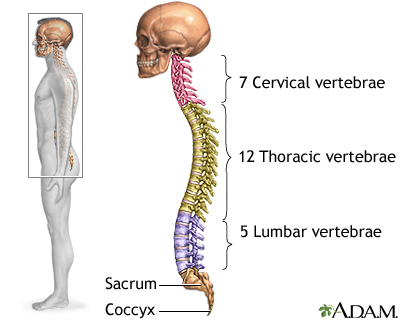

The spinal cord contains the nerves that carry messages between your brain and the rest of your body. The cord passes through your neck and back. A spinal cord injury is very serious because it can cause permanent loss of movement (paralysis), function, and sensation below the site of the injury.